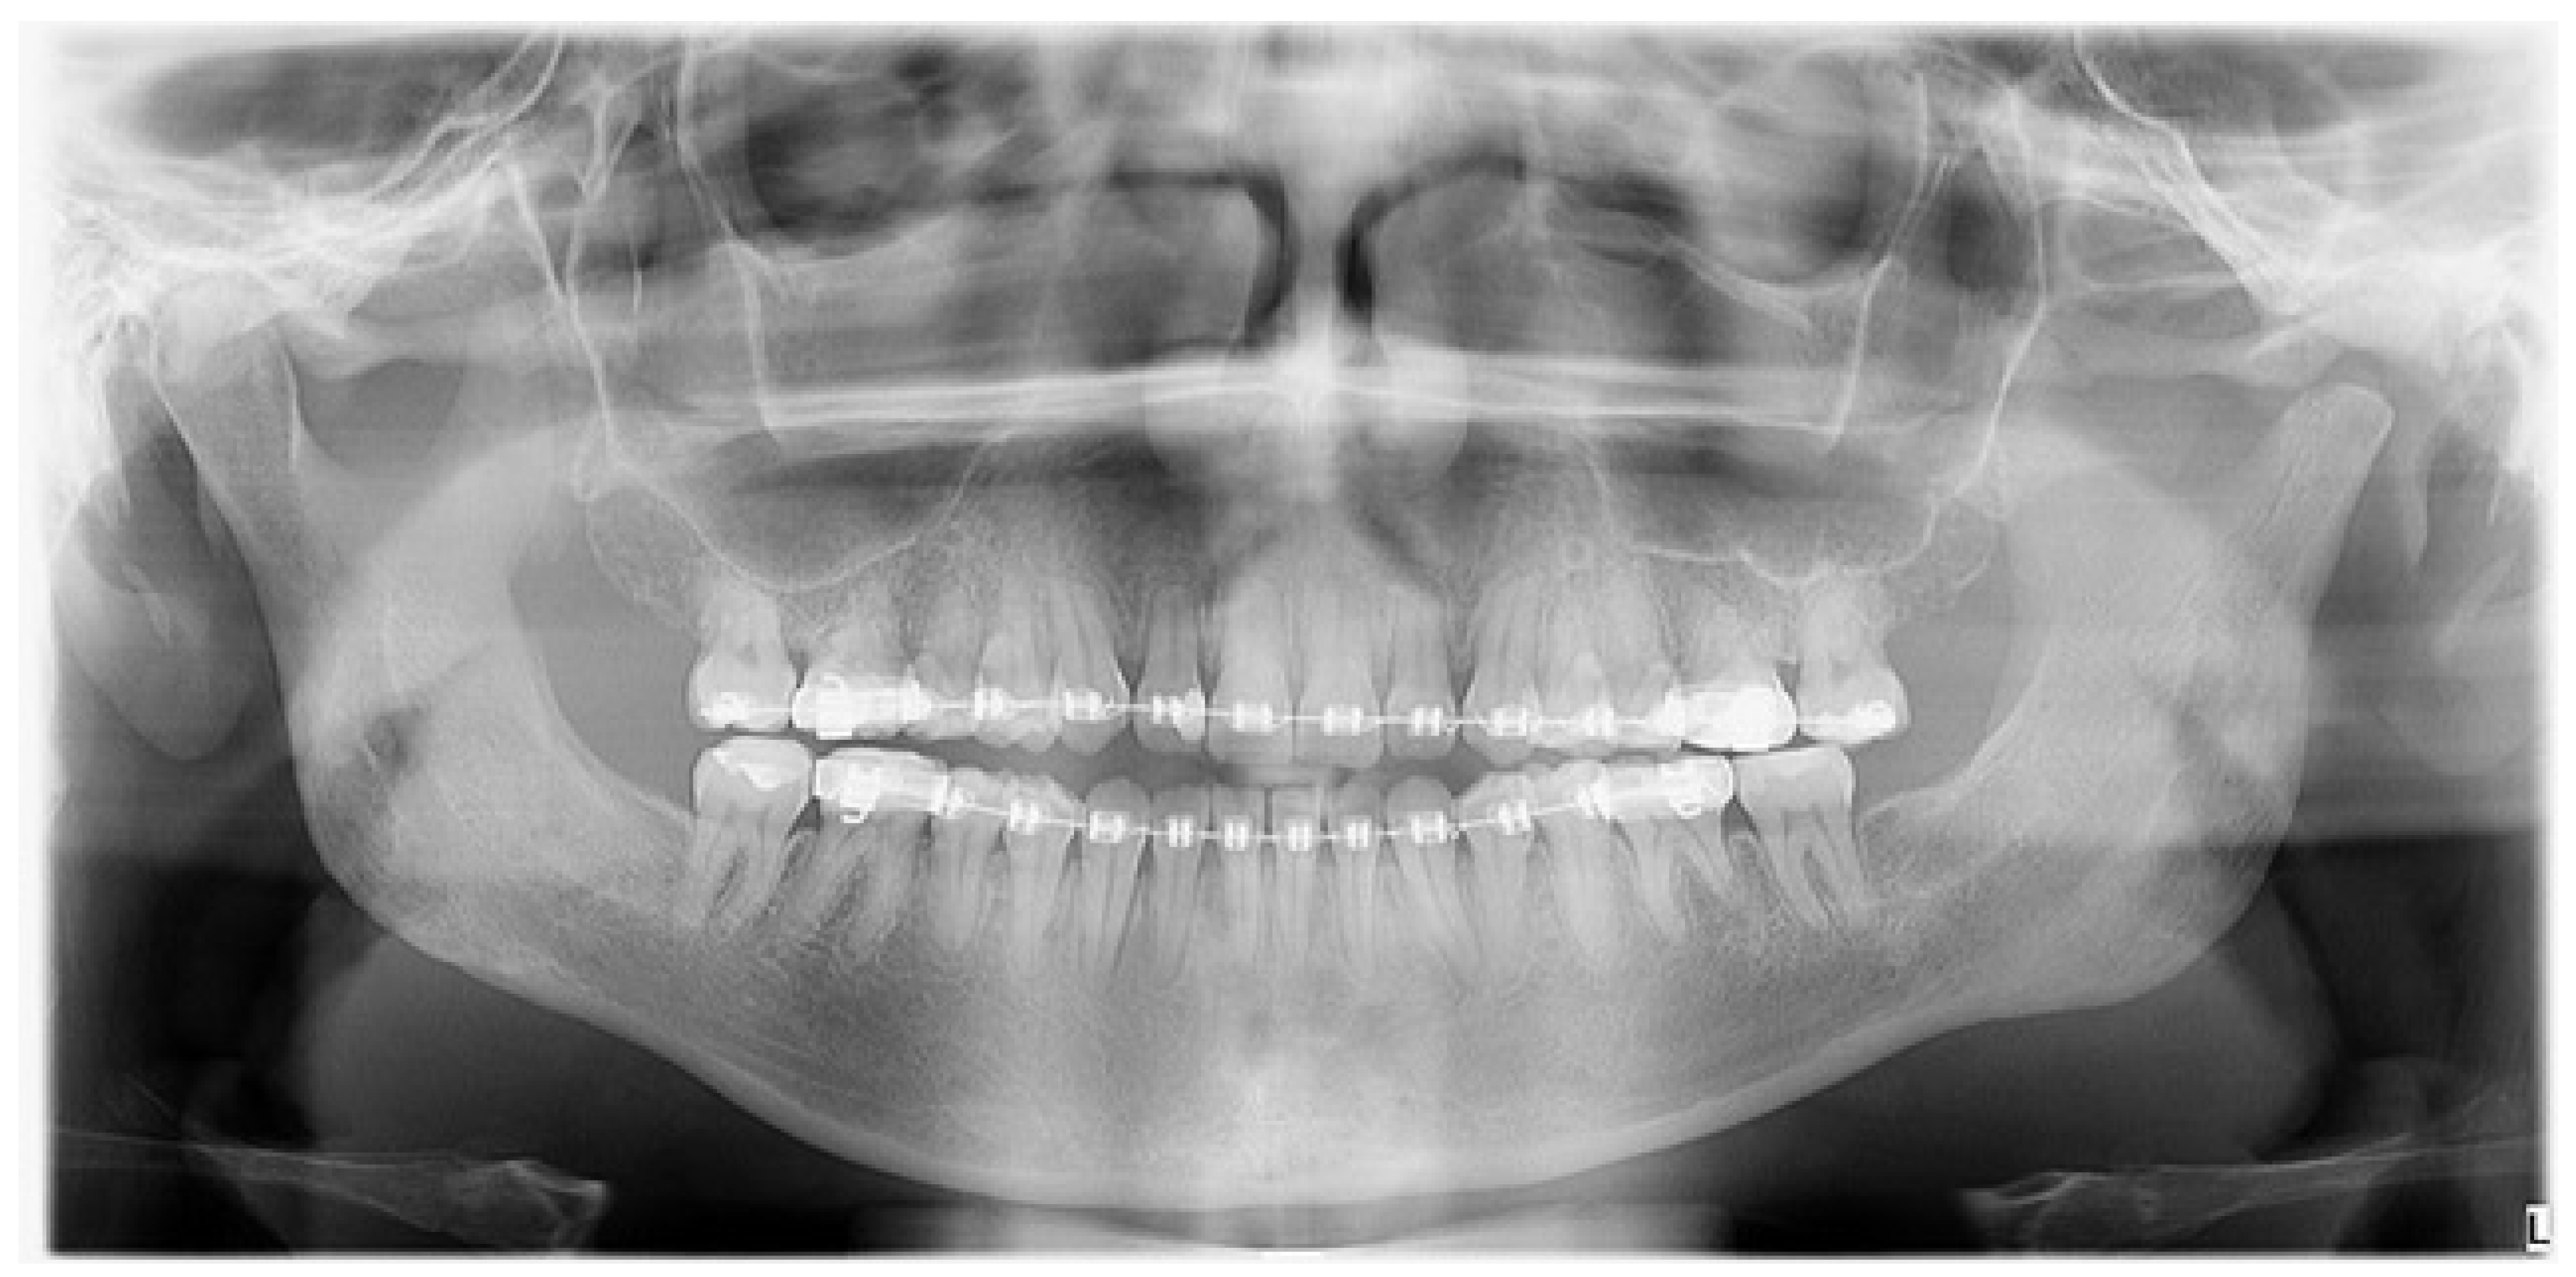

Figure 6.

A control panoramic radiograph after six months after a left-sided condylectomy. The jawbone remains asymmetrical with a deviated midline and inappropriate bite; therefore, the patient was scheduled for a revision BSSO surgery to establish more accurate jaw proportions. The scope and degree of the excised affected condylar head influences the later shape and size of the newly formed condylar head stump. Most authors recommend its 5 mm bone removal; however, in this presented case and in others, surgery excision must be bigger and is case-related. Achieving a stable position of the condylar head inside the glenoid fossa is an important matter [3,4,5].